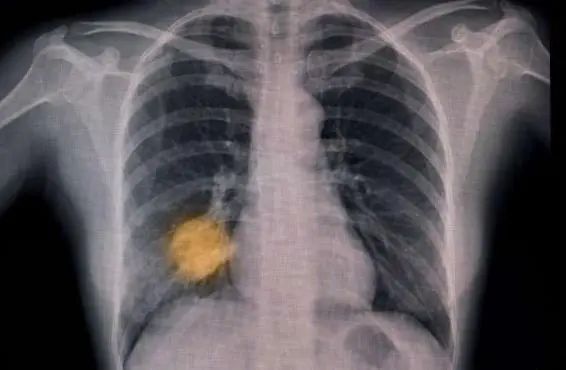

另一項(xiàng)進(jìn)行中的試驗(yàn)正在追蹤英國(guó)6家醫(yī)院的15萬(wàn)名患者,測(cè)試AI能否根據(jù)胸部X光片作出肺癌早期診斷,發(fā)現(xiàn)哪些患者需要當(dāng)天接受計(jì)算機(jī)斷層掃描(CT)。

人工智能工具的試驗(yàn)和兩年一次的篩查有望幫助人們更早地發(fā)現(xiàn)肺癌。

圖片來(lái)源:《自然·醫(yī)學(xué)》

通過(guò)CT篩查可以降低肺癌死亡率,然而其實(shí)施效果可能有限、緩慢且質(zhì)量參差不齊,部分原因是最初的CT掃描顯示9/10的人并沒(méi)有癌癥跡象。此次入榜的4-IN-THE-LUNG-RUN試驗(yàn),將檢驗(yàn)對(duì)于初次掃描中未見異常的人來(lái)說(shuō),每?jī)赡暌淮蔚姆伟┖Y查(使用CT掃描)與每年一次的篩查在預(yù)防癌癥死亡方面的有效性是否相同。